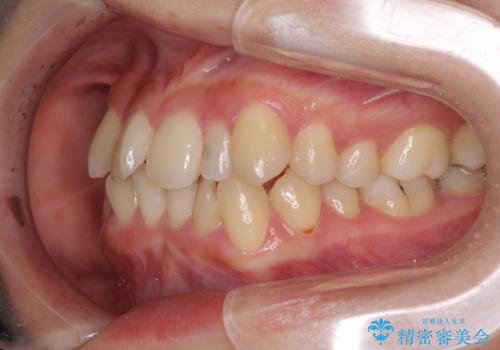

八重歯の抜歯矯正 補助装置を用いたインビザライン矯正

- 上顎の重なっている前歯を気にして来院された患者様です。

重なっている部分は抜歯が必要で、歯の移動量が多く、更には右側にずれている正中を改善する必要がありました。

インビザライン単体での治療は困難と判断し、補助装置により八重歯移動後にインビザラインを用いることとしました。

非常にしっかりとマウスピースを装着してくださいましたが、前歯の排列がなかなか仕上がらずに期間がかかってしまいました。